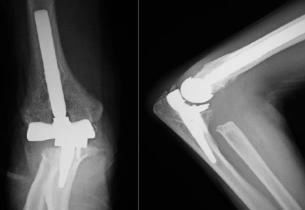

リウマチによる手・肘の変形に対する治療は一般的に難易度が高く、また習熟している施設は限られています。当院ではリウマチ手指や肘に対する人工関節手術を積極的に行い、良好な治療成績を得ています。また比較的若年の方で関節面が保たれている場合は可能な限り関節温存手術を行います。当院の担当医はリウマチ指の人工関節手術、人工肘関節手術、人工関節を用いない手指軟部組織形成術や肘関節形成術の経験も豊富です。人工関節は複数の種類がありますが、患者さんの状態に合わせて使い分けています。肩については、変形性関節症のところでも触れている、近年開発された肩の特殊な人工関節(リバース型)が導入されて以降、良好な成績が得られています。

人工肘関節手術後

・変形性肩関節症に対するリバース型人工肩関節(左:術前、右:術後)